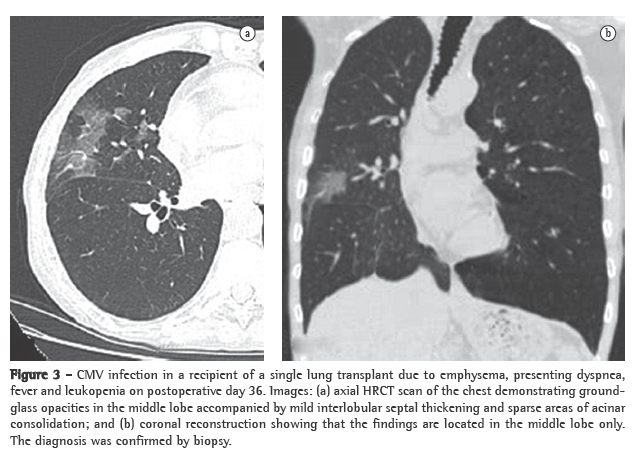

Pulmonary infections, which constitute a leading cause of morbidity and mortality, can occur at any time after transplantation.(3) The direct communication between the transplanted lung and the atmosphere facilitates infection. This is compounded by impaired mucociliary clearance and failure of the cough reflex.(11) The majority (65%) of transplant recipients develop infectious complications, 30% of which are extrapulmonary.(5) Most such infections involve the transplanted lung.(12) Bacteria and fungi are major causes of infection within the first postoperative month, whereas viral infections are more prevalent in postoperative months 2 and 3.(6)

Opportunistic infection occurs in 34-59% of lung transplant recipients.(13) Unfortunately, in patients with new opportunistic pneumonia, chest X-ray findings can be normal, and abnormal findings, when present, are often nonspecific.(11) Cytomegalovirus (CMV) is the most common opportunistic infection among such patients.(14) The incidence of CMV infection peaks between 1 and 2 months after transplantation, most cases occurring between postoperative months 1 and 12.(11,14) Infection with CMV can be primary and secondary. Primary infection occurs in over 90% of CMV seronegative patients receiving a CMV seropositive donor lung and becomes severe in 50-60% of such cases.(11) Secondary infection results from exposure to a different CMV strain or from reactivation of a latent infection in the recipient and is usually less severe than is primary infection.(11) Clinical manifestations of CMV infection include dyspnea, fever, malaise and leukopenia, although many patients with histologically proven CMV pneumonia are asymptomatic.(15) A diagnosis of CMV pneumonia is typically confirmed only after bronchoalveolar lavage and transbronchial biopsy. The radiologic ­manifestations of CMV pneumonia include, as shown in Figure 3, ground-glass opacities, interlobular septal thickening and consolidation, as well as diffuse reticular or reticulonodular opacities, nodules and small areas of effusion.(14) In lung transplant recipients with active CMV infection, chest X-ray findings can be normal,(11) CT scans better depicting the radiological manifestations of the infection, which almost exclusively affects the allograft. The most common CT manifestations are ground-glass opacities, tree-in-bud opacities, airspace consolidation, nodules, interlobular septal thickening, pleural effusions, thickened/enlarged pleura and bronchiectasis.(11-15) Other common viral pulmonary pathogens affecting this population include herpes simplex virus, adenovirus and respiratory syncytial virus.(11)